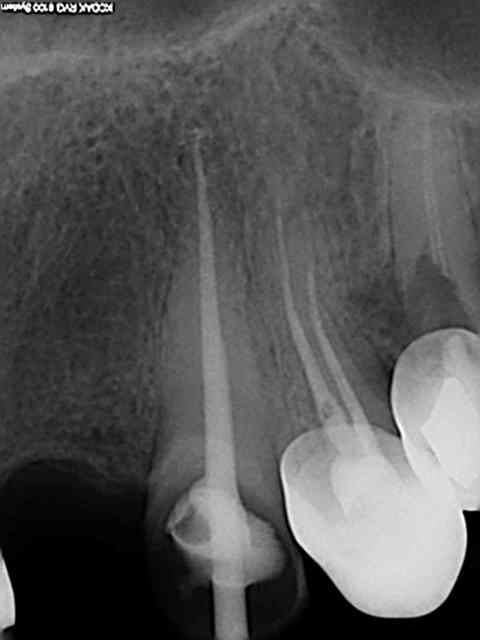

Effectivement le standard endo serait plutôt comme le disait MARC APAP N25 à 6% à l'apex.Je cherche(c'est personnel)

surtout à atteindre la LT validée par la radio+locateur d'apex si possible;j'utilise un cône de gutta hygenic médium fine ;je coupe l'extrémité à la réglette endo au "trou 35"

Je passe l'hero N20 6% au début à 2/3 de la LT supposée

avec récapitulation manuelle puis N20 4% à la LT suivie

de N25 4% ,N30 à 4% voir 6%

J'essaie de remonter chaque Niti en faisant un mouvement horaire le long des parois(environ 4 mouvements) tout cela avec beaucoup d'hypo(je regrette mais le dakin n'est pas validé par les endos exclusifs)je passe un endoflare mais pas au début=je crains une amorce de déviation du canal

Je suis conscient que mes endos pourraient être plus alésées

à l'apex ;mais j'ai une bonne herméticité (vérifié par un CBCT acheté récemment)

J'ai mis des radios de RTE dans le post consensus "eugénolien" pour une dentisterie du XXI siècle

Le Mac Spadden a changé mes endos;le lentulo n'est plus d'actualité même si une endo cône scellé est très radio opaque;l'endo 3D reste le standard.Il faut un bon "tug back"

sinon il y a un risque réel de faire partir de la gutta dans le périapex quelquefois du ciment canalaire (cela crée des"puff" plutôt positifs.Je prends un Mac spadden de gros diamètre 50;cela casse souvent mais se récupère tout le temps;casse très haute vers le mandrin.Tu connais le lentulo

avec ses dépassements fréquents de pâte canalaire dans le périapex(pour moi à abandonner depuis longtemps....)

Ta triade digue+hypo+Niti est pour moi le standard il faut rajouter le mac spadden (j'ai le système B et j'avoue je ne le maîtrise pas je remonte souvent le cone de gutta en chauffant et même en attendant avant de remonter)